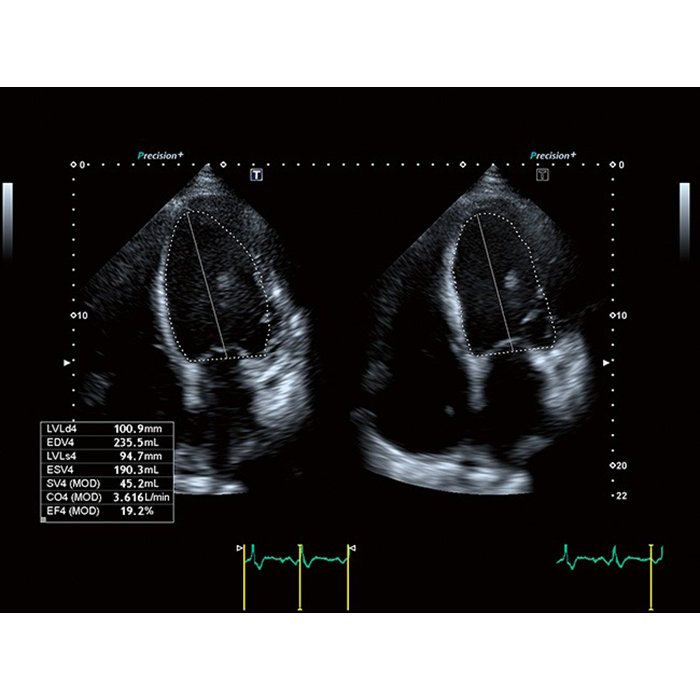

Система Aplio a450 – это решение с полным набором программно-аппаратных средств, которое можно масштабировать для выполнения самых различных диагностических задач.

Высочайшее качество изображений и удобный интерфейс, унаследованный от самого совершенного оборудования Canon Medical, помогут обеспечить высочайшую продуктивность и скорость работы.

Современные технологии визуализации помогают еще больше повысить точность получаемых клинических данных для наиболее сложных случаев.

- SMI. Опция, упрощающая визуализацию микроциркуляторного русла. С ее помощью обследуются сосуды с низкой интенсивностью кровотока, изучаются наиболее тонкие структуры. SMI упрощает диагностику новообразований, минимизирует вероятность ошибки.

- Precision Imaging (прецизионная визуализация в результате получения и обработки данных от смежных сигналов))

- ApliPure+ (повышение контрастности изображений)

Технология получения и отображения информации о жесткости ткани, возможность проводить оценку динамики перфузии органов, тканей, образований, простой межреберный доступ благодаря специальным конвексным датчикам, возможность совмещать картинку в режиме реального времени с прежними данными МРТ, КТ, УЗИ, детальная визуализация плода в 1 триместре, технология трекинга миокарды и другое. Конкурентная цена и широкая продуктивность УЗ сканера Toshiba (Canon) a450 делают его покупку выгодным капиталовложением и выводят медицинское учреждение на более высокий уровень обслуживания пациентов.Область применения

Аппарат является универсальной моделью и подходит для разных областей диагностики. Его используют в кардиологии, педиатрии, сосудистой хирургии и т. д. Система совместима со многими преобразователями Aplio и позволяет врачам ставить точные диагнозы. Подходит для стационарных отделений и поликлиник, может использоваться в больших медицинских центрах.Система Canon Aplio A450 поддерживает исследования

- Кардиология